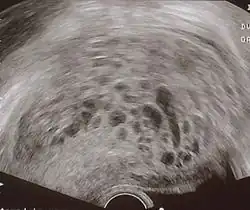

Диагноз пузырного заноса устанавливается при ультразвуковом исследовании. Вместо нормальной структуры плодного яйца обнаруживается пёстрая картина, получившая название «снежной бури». В яичниках определяются лютеиновые кисты. При исследовании гормонов отмечается высокий уровень хорионического гонадотропина (ХГЧ), иногда многократно превышающий уровень при нормальной беременности.